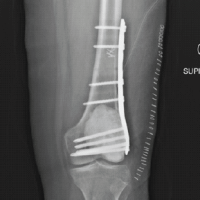

The 12-year-old sister, similarly, had bilateral cleft hands and feet; however, her left hand had an abnormally broad commissure, which prevented “pinching” of the digits, resulting in slight functional impairment (Fig. 2).

Figure 2: (a) 12-year-old girl with bilateral cleft hands; (b) Radiographs of both hands; (c) Function of left hand marginally reduced compared to right; (d) Bilateral cleft feet; (e) Radiographs of both feet; (f) Bottom view of both feet; (g) Ectodermal dysplasia in the form of sparse eyebrows and scalp hair.

Her right hand, on the contrary, had good prehensile function. She exhibited hypotrichosis over the scalp and eyebrows with no other significant abnormality on cutaneous, oral, or general physical examination. Radiographs of both hands revealed the absence of the central ray bilaterally, with triphalangeal thumbs. Radiographs of both feet showed the absence of the central 3 rays bilaterally. The USG abdomen and pelvis were normal.

Management

The patient and her mother were informed about the pros and cons of surgical reconstruction of the left hand, and the possibility of hand function remaining unchanged following any intervention. A 6-month follow-up to look for worsening hand function was advised.